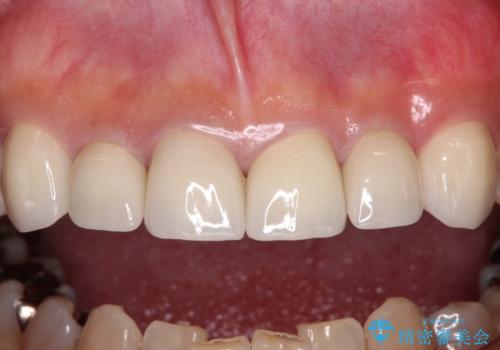

長年前歯の色の違いに悩んでいらっしゃったようですが、仮歯に変えた時点で統一感のある白さとなり喜んで頂きました。

わずか1ヶ月の間にとても自然な仕上がりのセラミッククラウンが装着され、患者様には大変満足していただきました。